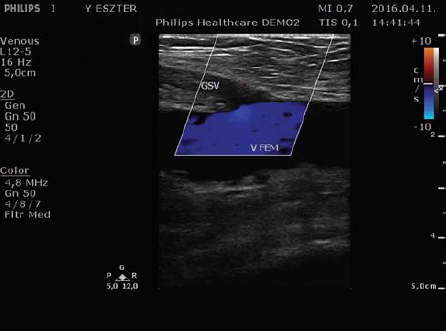

A graviditás során bekövetkező érelváltozások célja az uterus és ezáltal a magzat jobb oxigén és tápanyag ellátása. Az erek kitágulása folytán több vér áramlik ide. Úgy tűnik, az értágulatot létrehozó mechanizmusok azonban nem csak a célszervre hatnak, hanem a már eredendően a kétlábon járás miatt túlterhelt alsó végtagi felületes visszerekre is. Az alsó végtagi felületes vénák graviditás során létrejött tágulatát ultrahang vizsgálattal (UH) le is mérték (9, 10).

1. ábra.

Terhességi varicositas.